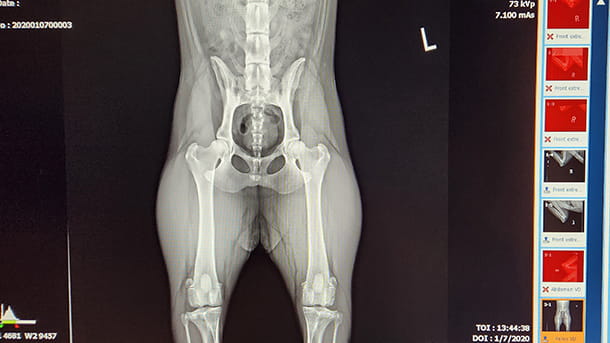

• OFA x-ray of a dog

Our hospital offers OFA x-rays for identification of hip and/or elbow dysplasia in dogs. OFA is the Orthopedic Foundation for Animals and is an organization that was created to aid breeders in helping reduce the incidence of hereditary health issues. Dogs must be over 2 years of age and the x-rays must be taken using heavy sedation for patient comfort and accurate positioning.... Read more